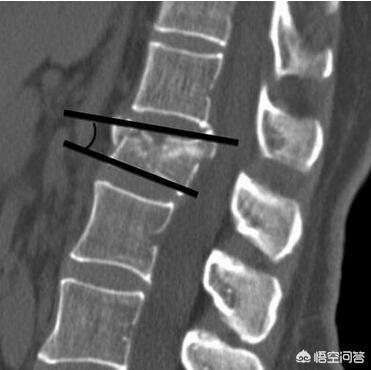

Q頭部打撲による頭蓋骨骨折が,死亡や重傷という事態になりやすいのはなぜですか。 脳ヘルニア, 脳挫傷, 頭蓋内圧亢進, 頭蓋骨骨折 A 頭蓋骨骨折とは,言うまでもなく脳を保護する頭蓋骨が壊れたということです。 頭蓋骨が壊れることで脳が損傷こと手術 内側に陥没した頭蓋骨が、脳に圧迫や損傷を与え障害を及ぼしている場合、陥没骨折整復術が行われます。 手術の必要性は、陥没の程度に比例して、日本のガイドラインを手術適用の目安としています。 ① 1cm以上の陥没 ② 前額部など美容上問題 交通事故で頭蓋骨骨折を負った場合、保存療法や手術で治療を行いますが、後遺症が残る可能性もあります。 交通事故の被害にあい、後遺症が残った場合は後遺障害等級認定を申請し、加害者に 後遺障害慰謝料 や 逸失利益 を請求するようにしましょう。